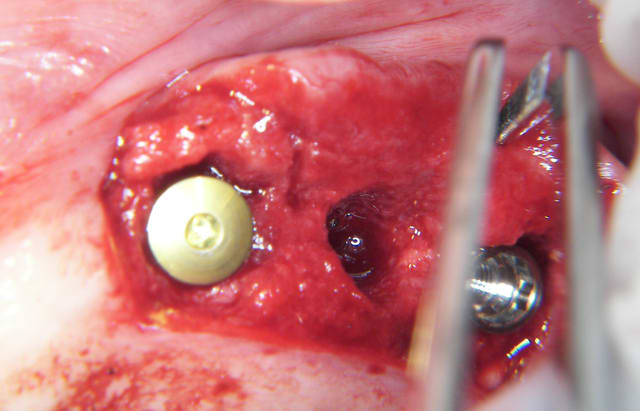

voici peut être une autre solution qui te satisfera d'avantage car beaucoup plus simple à mettre en œuvre.

c'est une simple ROG avec des vis pour maintenir l'espace sous la membrane.

As-tu fait de l'ostéotension ou similaire pour augmenter l'apport sanguin ?

As-tu utiliser du PRF pour améliorer ostéoconduction?

comment as-tu obtenu la laxité gingivale pour fermer sans tension?

n'as-tu pas peur que malgré tout ça bouge avec la mastication?

Combien de temps laisses-tu cicatriser avant de réintervenir?